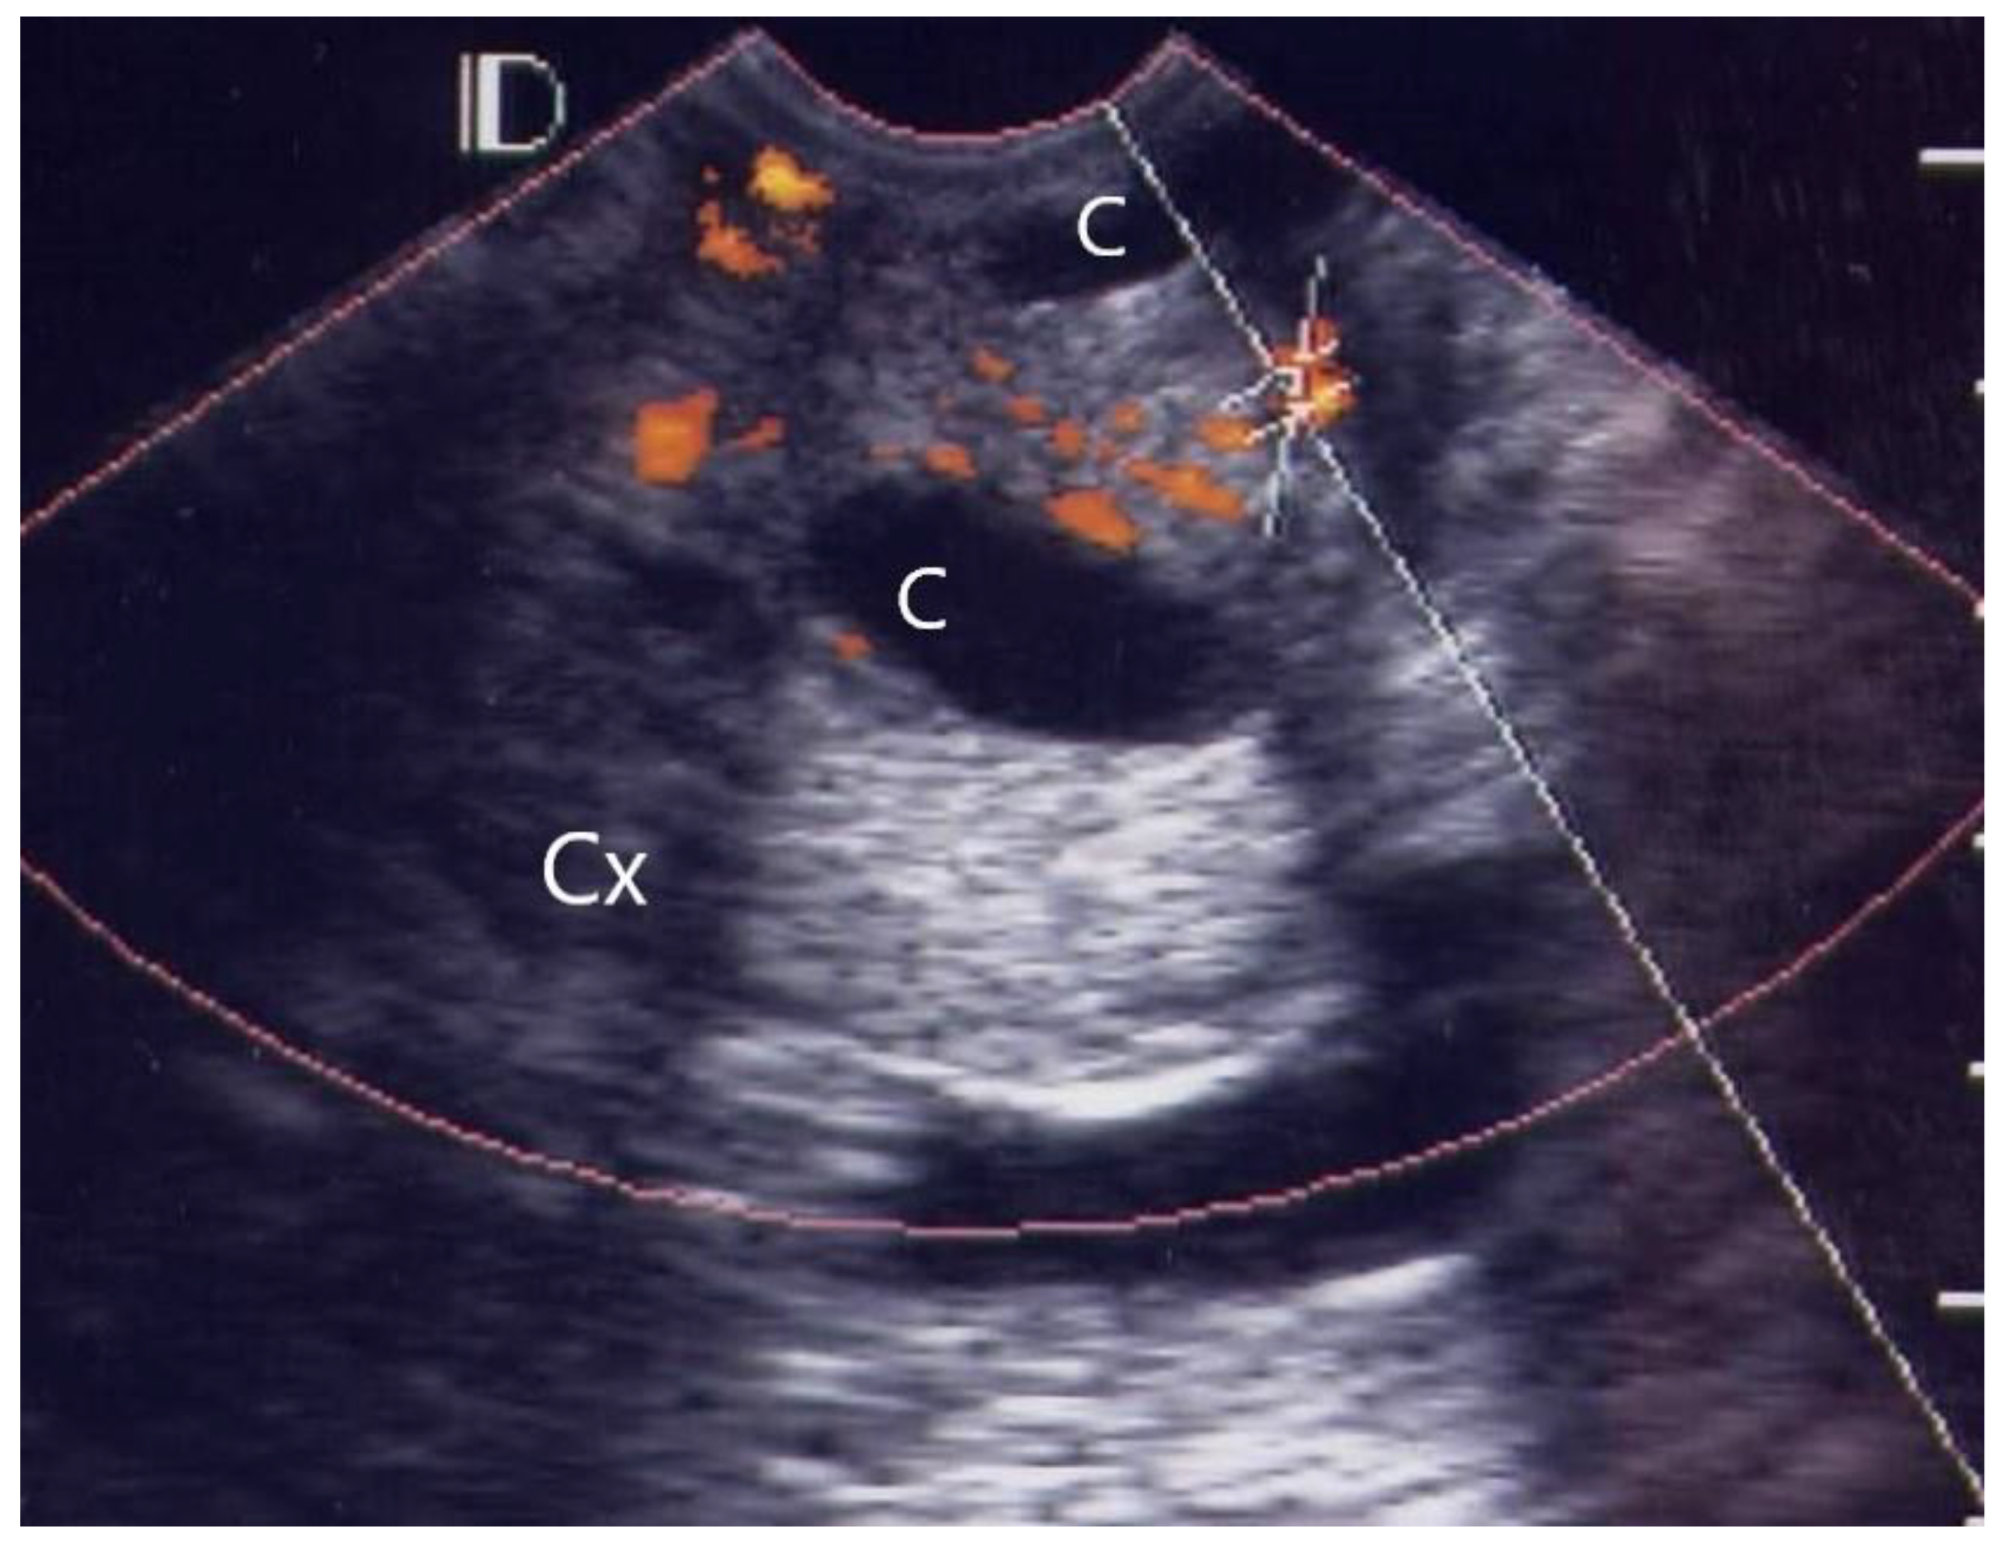

3.1. Visual Grading of Vascularity Findings on TV-PDU

| Grade 0 | Absence of vascular hot spot |

| Grade 1 | <5 vascular spots, not involve the endocervical canal |

| Grade 2 | >5 vascular spots, not involve the endocervical canal |

| Grade 3 | Involved the endocervical canal, without involved whole endocervix |

| Grade 4 | Involved the whole endocervix |